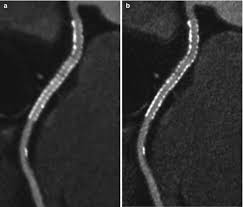

Evaluation Of Soft Plaque Stenoses In Coronary Artery Stents Using Conventional And Monoenergetic Images First In Vitro Experience And Comparison Of Two Different Dual Energy Techniques Hickethier Quantitative Imaging In Medicine And Surgery

Evaluation Of Soft Plaque Stenoses In Coronary Artery Stents Using Conventional And Monoenergetic Images First In Vitro Experience And Comparison Of Two Different Dual Energy Techniques Hickethier Quantitative Imaging In Medicine And Surgery from cdn.amegroups.cn